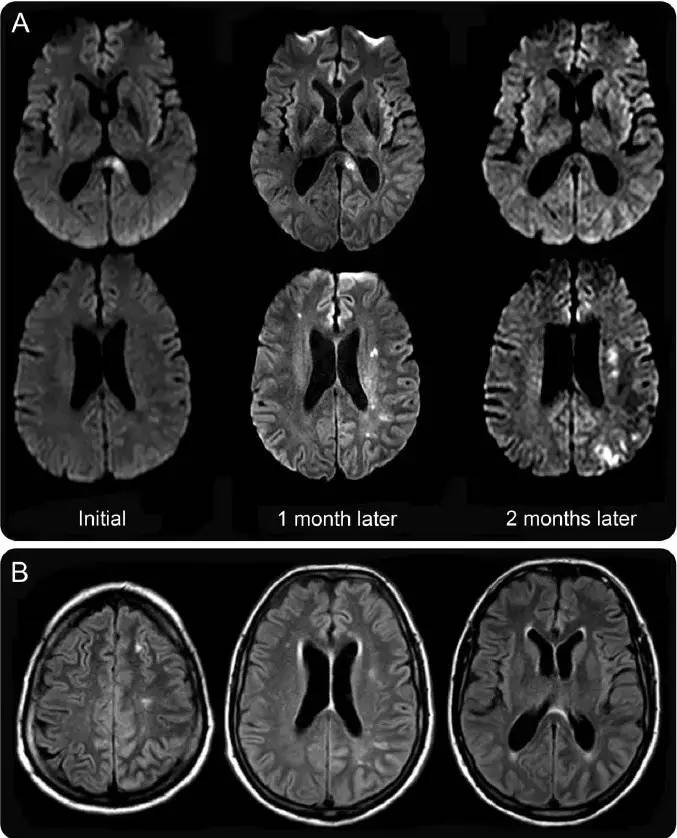

下图A,不同时期DWI影像,提示不同时期梗死灶逐渐增加。下图B为Flair。